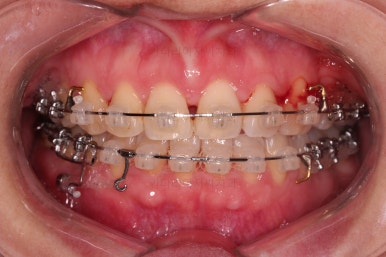

브라켓을 부착합니다.

이번 환자분이 선택하신 장치는 데이몬 클리어라고 하는 자가결찰 세라믹 장치인데요.

일반적으로 흔히 아시는 클리피씨 장치에 비해서 철사를 잡아주는 뚜껑까지 세라믹으로 되어 있어서 아마도 현존하는 세라믹 장치 중에서는 가장 심미적인 장치라고 볼 수 있습니다.

대신, 세라믹으로 되어 있다보니 강도 때문에 부피는 조금 더 커진다는 단점은 있긴 합니다.

치열이 매우 가지런해졌고, 아래 앞니 사이 틈새도 점점 오므려져 가고 있습니다.

발치 공간을 적극적으로 줄여 나갑니다.

이 과정에서 입매, 앞니 각도, 정중선 등을 신경 써줍니다.

아무래도 상하좌우 비어 있는 공간의 위치가 모두 달랐기 때문에 자칫하면 중앙선이 한 쪽으로 쏠려버릴 수 있기 때문이죠.